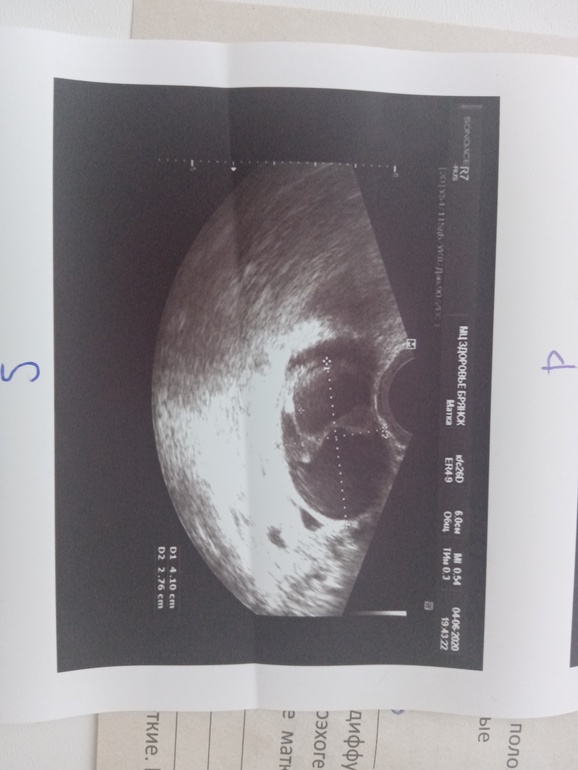

Сегодня попала наконец на узи.

УЗИ прилагаю, жду помощи

Помню после зб у меня стали образовываться кисты на яичнике. Потом рассасывались. Врач сказал, что при кистах не может быть беременности, так как это сбой цикла. Но я упорная, сказала, что будет) и в следующем месяце пришла уже к нему на узи с «сюрпризом». Спокойно выносила и родила сына. Так что это и от самой кисты зависит, и от организма. Потом ещё была киста 8 см после рождения сына (ему было 7 месяцев), что-то покололи мне, в следующем цикле после менструации почти рассосалась. Но тут надо смотреть динамику и наполнение её.